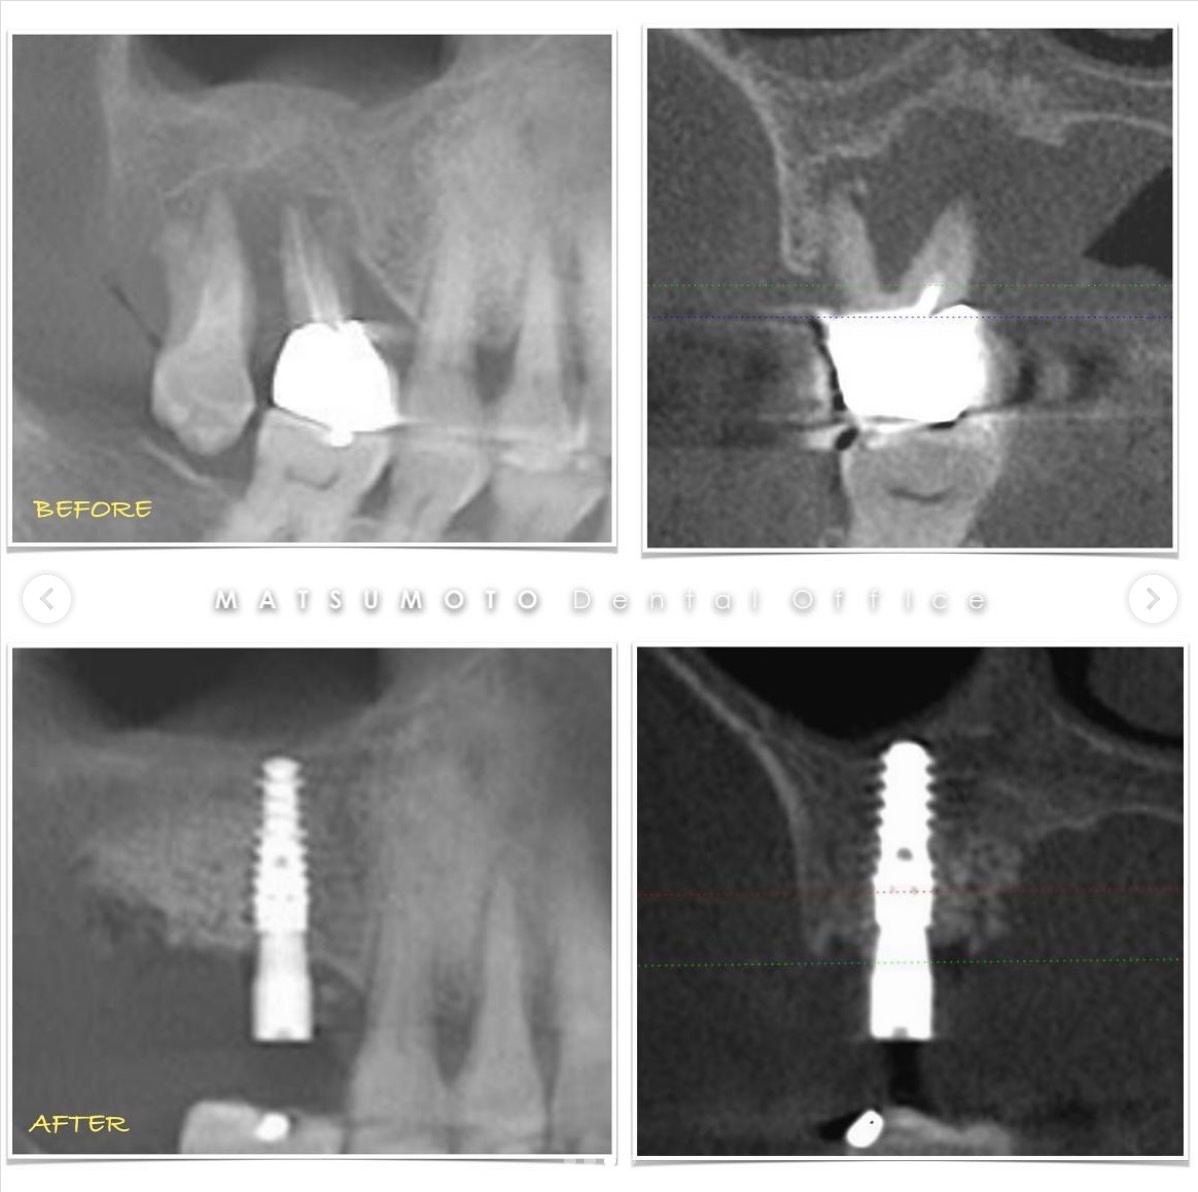

症例紹介27:インプラント治療/下顎6本《70代男性》

治療内容:

保存不可能なインプラントを抜去して、新しいインプラントを入れ変えました。

インプラントが良い位置に入ってることにより、安定した予後が期待できます。

インプラントガイドを使用することによってこのような結果を出すことができます。

術前の診査診断

術前写真

上顎:インプラントが不適切な位置に入っており、仮歯を無理やり入れている状態。

下顎:インプラント周囲の骨がなくなっており、保村不可能な状態。

パノラマX線

上顎:インプラントは保存できる状態。

下顎:インプラントを含め全て保存不可能な状態。

All-on-6を終えて

最終補綴

上顎:ロケーターアバットによる義歯

下顎:フルジルコニアブリッジ

治療のリスクと副作用

治療期間:約半年

治療費:¥3,850,000(税込)

リスク:インプラントのネジが緩むことはありますが、なるべく連結しないような設計にしているので、問題をはやく見つけやすくしております。